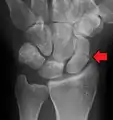

Radiolucency around a 12 days old scaphoid fracture that was initially barely visible.[13]